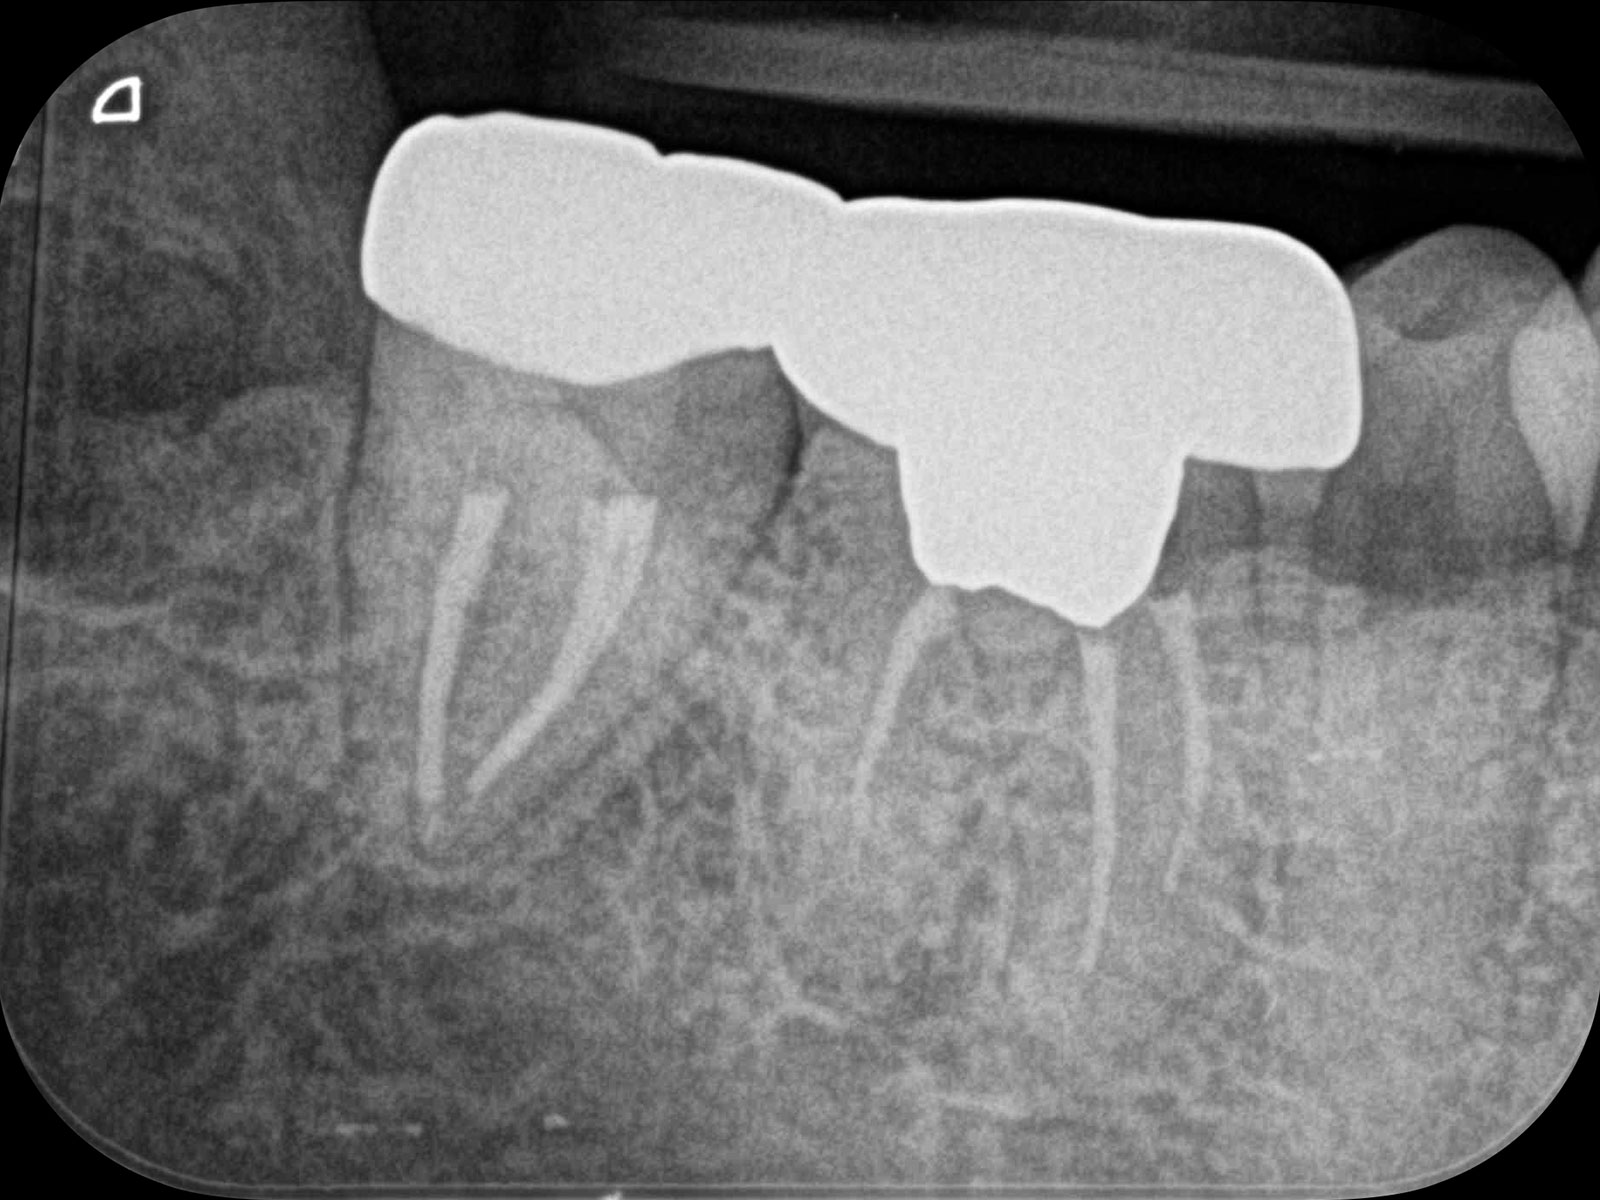

主訴: 噛むと痛い、左で食べれない。他の病院で神経が見つからない。根の先に病気がある。

通常だと手立てがなく、抜歯しかない歯も外科(根尖切除術)で治すことができます。

丸の部分が病巣です。CT画像によって、左の画像(Before)では黒く映っている病巣が右の画像(After)ではなくなっていることが確認できます。レントゲン画像ですと、ここまでクリアに写りませんので、病巣を見落としてしまう可能性があります。